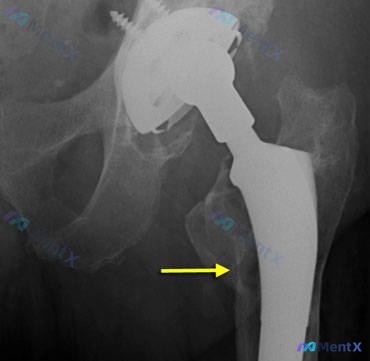

病例资料整理 患者信息:72 岁女性 既往史:18 年前行初次全髋关节置换术(THA) 主诉:前来接受评估 影像发现: - 放射照片显示右侧全髋关节置换术后状态。 - 股骨假体柄内侧下方可见透亮区/骨质缺损影(箭头所示),边缘可见骨质增生或硬化。 - 假体周围骨小梁结构紊乱,提示局部骨质溶解。 病理...